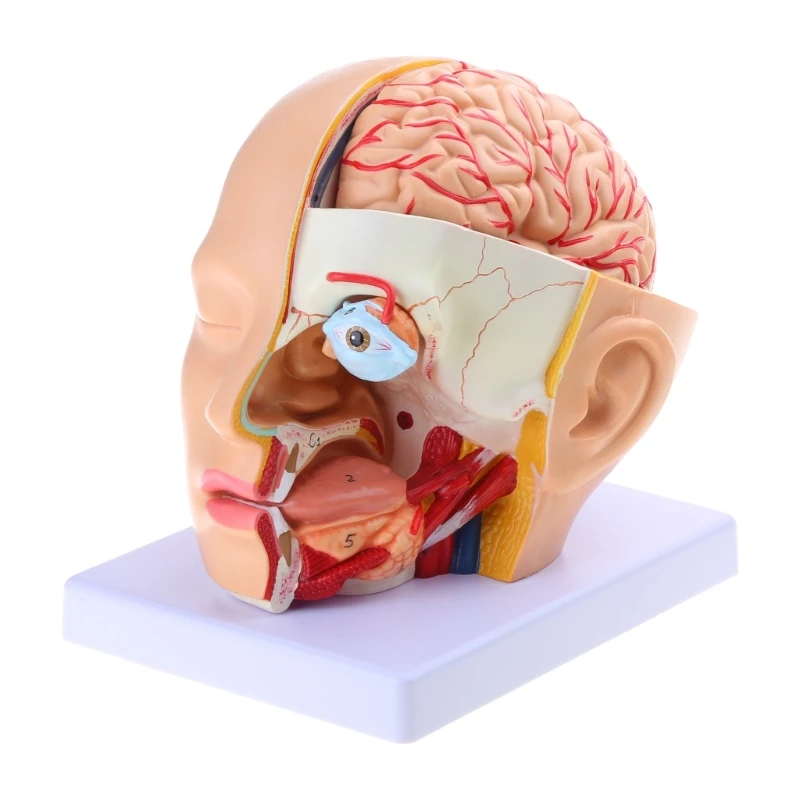

Анатомия: Задняя соединительная артерия мозга